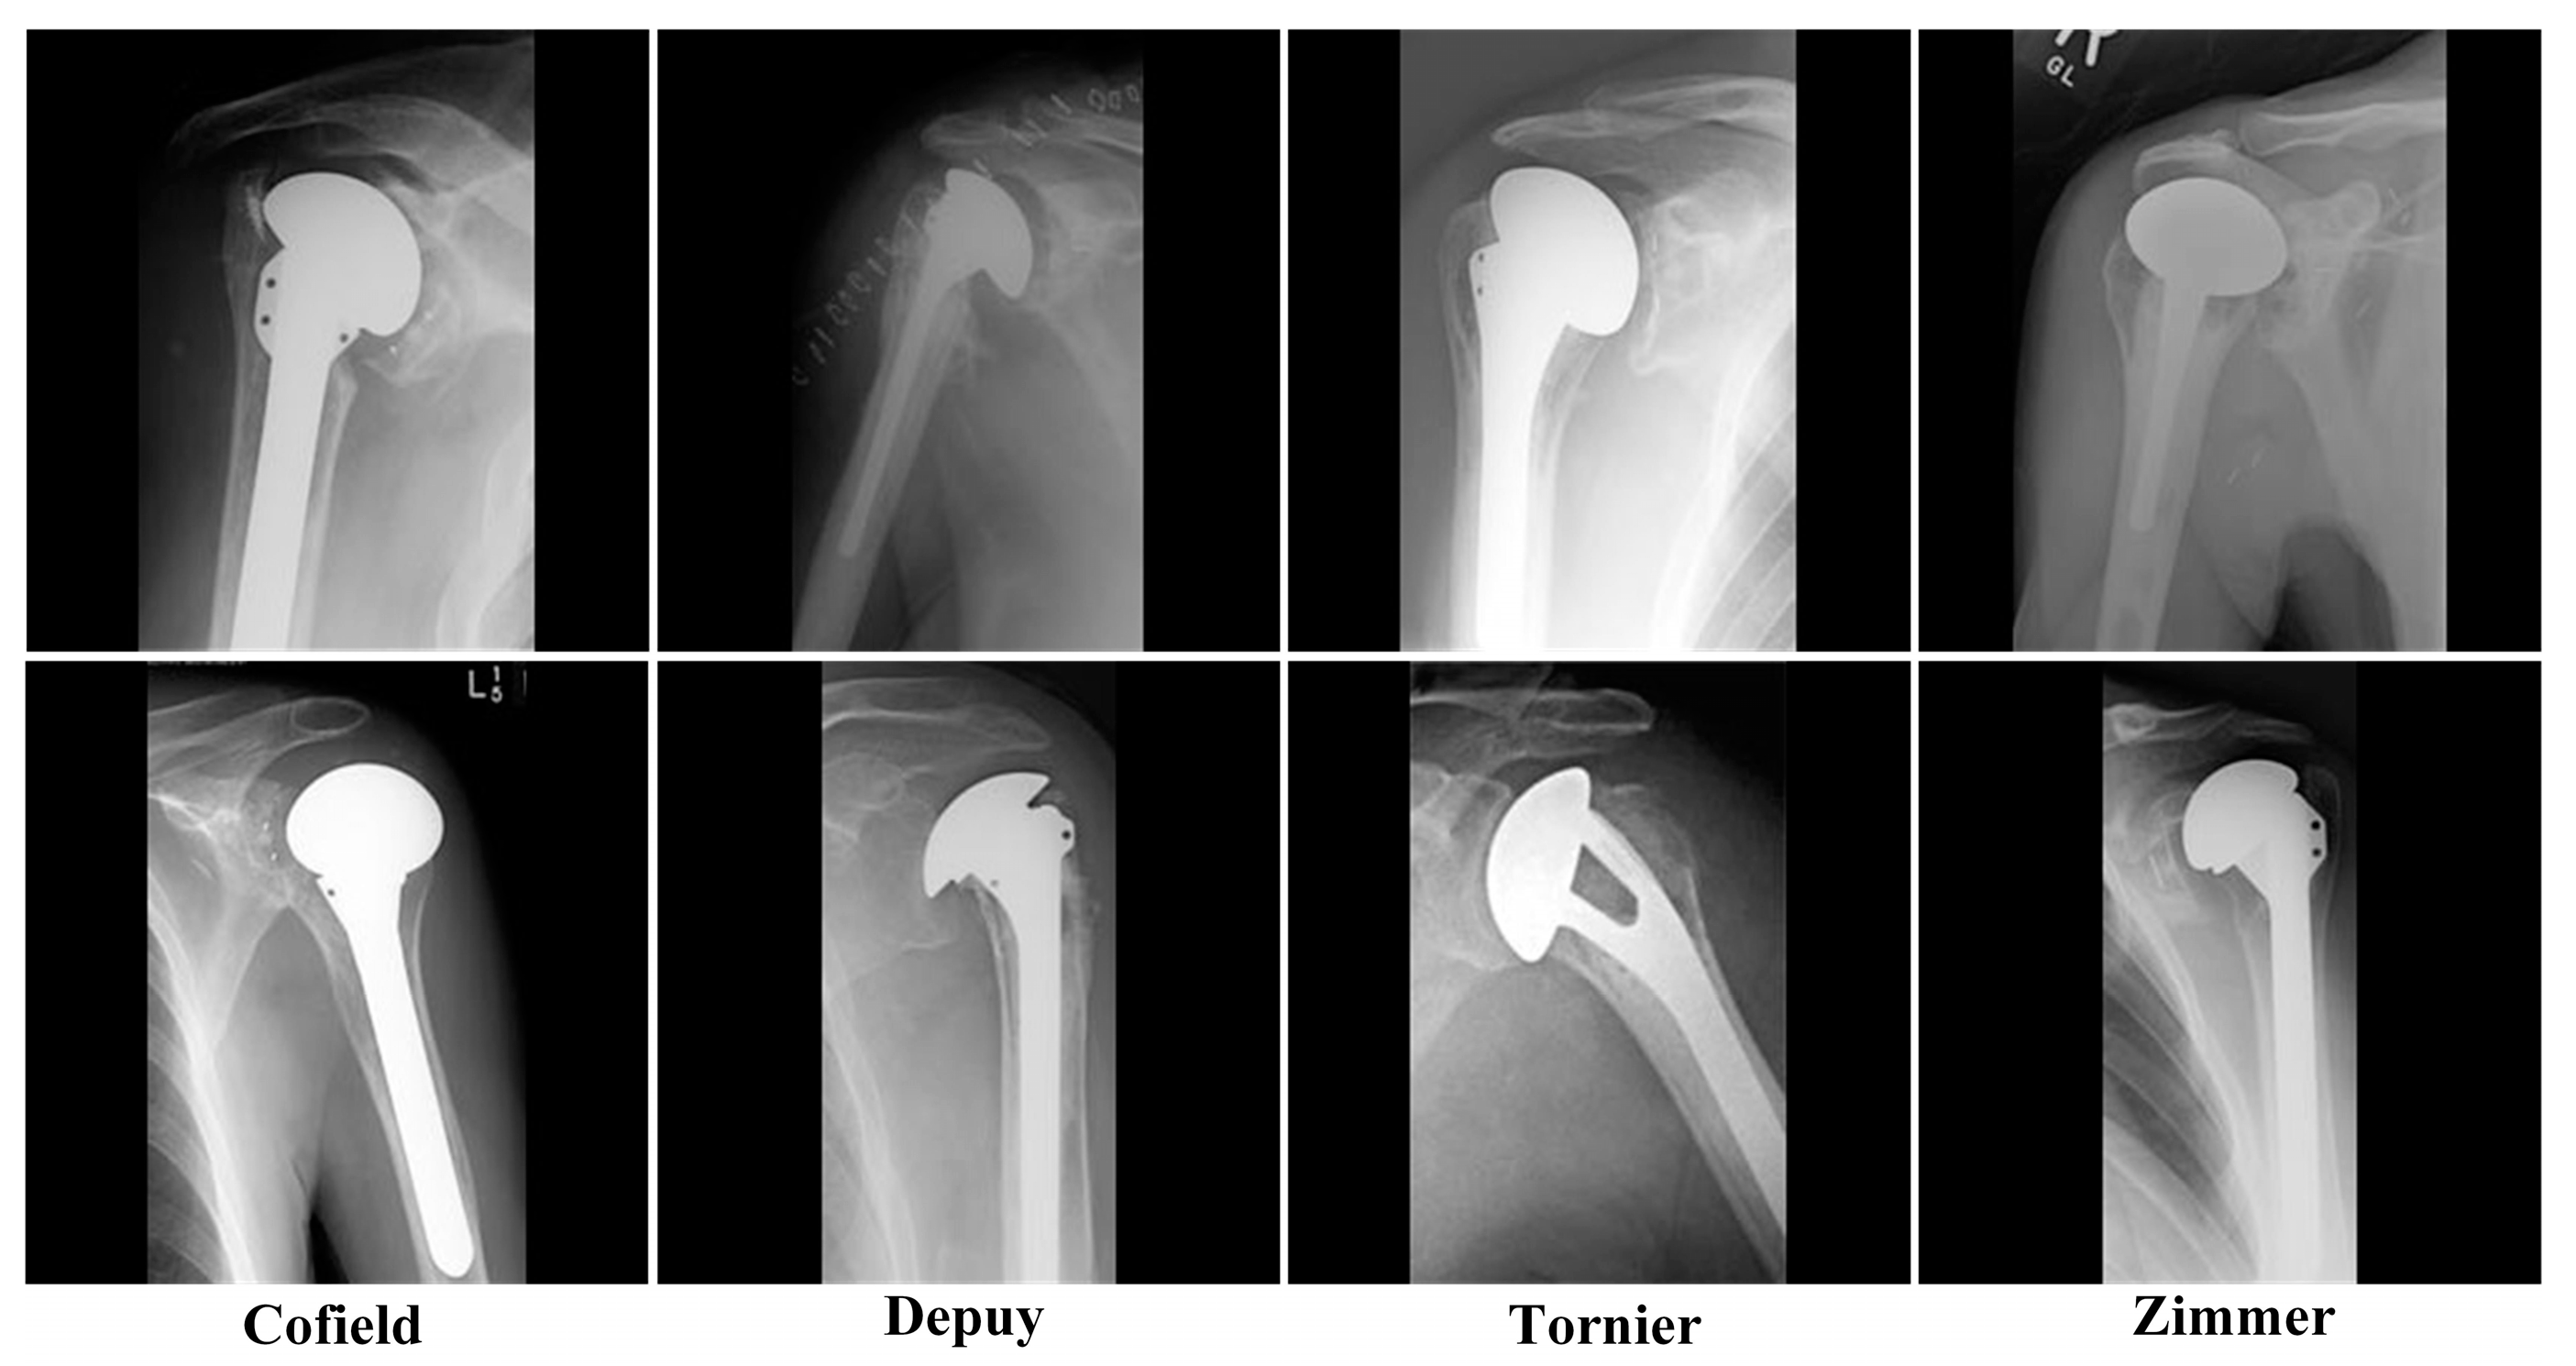

The dataset [13] used in the study includes 597 X-ray images of shoulder implants. In the dataset, there are X-ray images of 4 different shoulder implant manufacturers: 83 Cofield, 294 Depuy, 71 Tornier, 149 Zimmer. In Figure 1, X-ray samples of 4 classes in the dataset are given. Images are variable and have relatively low image resolution. The longest dimension of most of the images is 250 pixels. This dataset is publicly available, and all of the studies using this dataset will presented in Section 3.

Figure 1. Samples from the dataset.